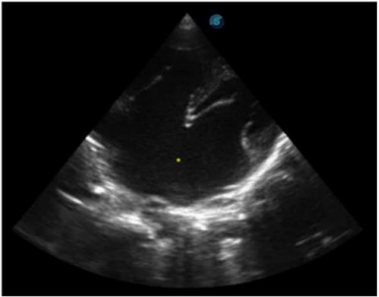

On radiological examination, Echocardiography revealed a common atrium due total absence of the interatrial septum, mild tricuspid regurgitation, preserved ejection fraction of 58.9% and preserved ventricular geometry (Figure 1). Ultrasonography of the abdomen revealed transposition of the major visceral organs (the spleen and stomach are located on the right side). Liver is enlarged occupying the whole upper part of the abdomen. There are two main hepatic veins (with 3 branches, each) joining before draining directly to the common atrium (CA) and left-sided inferior vena cava (IVC) (Figure 2).

Figure 2: (a)Ultrasound showing liver with two lobes each drained by its own three hepatic veins * (b)Ultrasound showing left placed inferior vena cava and right placed stomach (S).